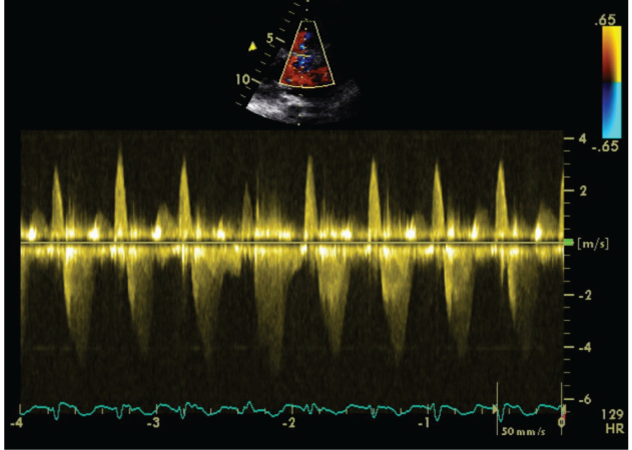

We carried out an Exercise Stress Echocardiogram using a semi-supine bicycle using WHO protocol using a 3-minute step protocol of 20-40 watts at 60-75rpm until volitional fatigue. All basic haemodynamic parameters were recorded at rest and at each stage of exercise (BP, heart rate, Oxygen saturation, electrocardiogram). We assessed his shunt in para-sternal long axis window (PLAX). Consultant cardiologist and senior cardiac physiologist carried out the test. We used colour doppler across interventricular septum to identify the VSD. Once it was identified, we tilted the probe to optimize VSD capture. Sample volume was then placed through VSD to obtain pulsed doppler images at rest (Figure 1). Similar pulsed doppler images were obtained at peak exercise (Figure 2). We did direct shunt volume assessment using velocity time integral (VTI). We averaged all VTIs obtained for five cardiac cycles.

Figure 1 Echocardiographic pulse wave doppler signal at rest.

Averaged VTI at rest for left to right (L-R) shunt was 26.32cm and at stress was 21.6cm. Similarly VTI at rest for right to left shunt (R-L) was 78.08cm and at stress was 79.44cm.